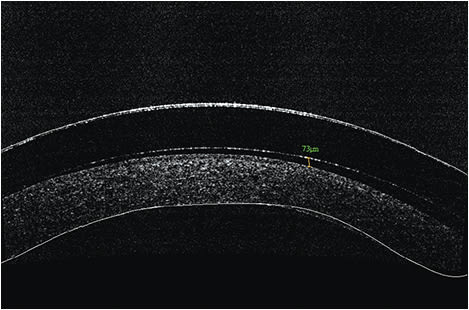

Fitting scleral lenses is typically done by selecting the best sagittal height match between the cornea and the contact lens. The desired central vault over the corneal surface varies according to lens design and the clinicians’ desired fitting philosophy for each individual patient. Typical values will range from about 150 to 400 microns. Figure 1 shows an example of excessive sagittal vault. Figure 2 shows an example of insufficient vault. And, Figure 3 shows an example of a desired amount of vault. Note: Scleral lenses settle into the bulbar conjunctiva over time following application. As such, central vault values can decrease by as much as 100 to 200 microns over a few hours after application.

Figure 2. Sagittal height of 40 to 90 μm = insufficient vault.